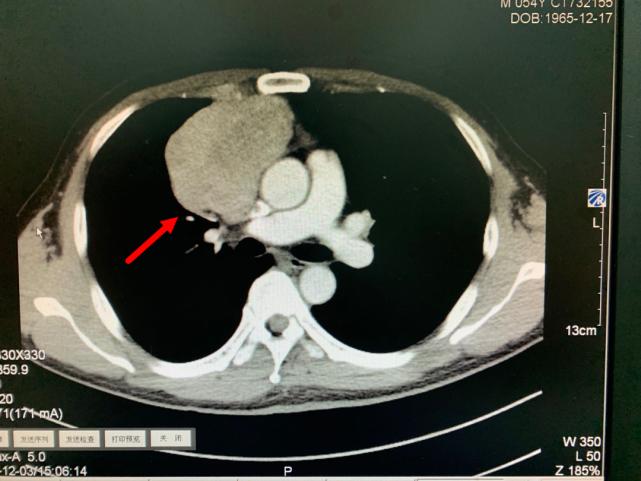

箭头所指为巨大纵隔肿瘤

今年11月份,老方因“肠炎”在浙江省立同德医院肛肠科住院。“新冠”期间住院需要常规做胸部CT筛查,检查出来的结果却让他和医生们大吃一惊,胸部CT显示:胸腔内存在一个巨大肿瘤即纵膈肿瘤,大小约10.0cm×6.5cm×7.0cm,大小和一个成人男性拳头差不多。肿瘤紧靠着肺部、心脏及大血管,且与部分大血管有粘连,对重要的脏器已经造成了挤压。在确定胃肠道没有严重病患后,老方被转入心胸外科进一步作检查、治疗。

叶中瑞主任医师通过进一步增强CT检查发现,老方体内的肿瘤巨大、与相邻的重要脏器粘连,界限不清,手术难度较大,且微创手术不适合,于是采取正中劈开胸骨的手术方式。手术过程顺利,术后恢复良好。第二天即下床活动。术后病理结果显示:纵膈肿瘤性质为中度恶性的胸腺肿瘤,后续还需要做进一步的放射治疗,以防止复发。老方在庆辛之余,他告诉叶中瑞主任医师,自己从今年开始每年都按时做体检,争取做到疾病早发现、早治疗,避免错过疾病的最佳治疗时机。